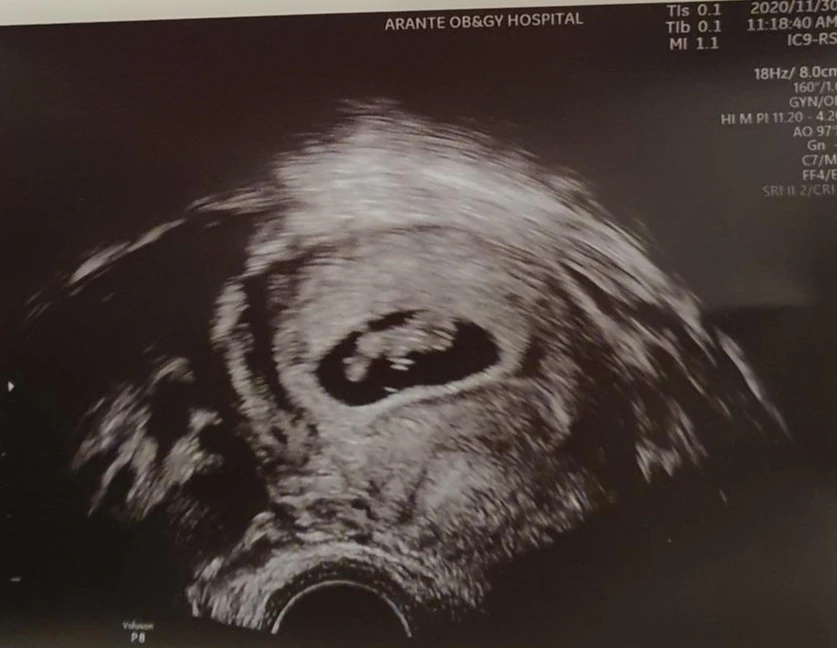

꽃도 사고 책도 보고 게임도 하고(아내 친구 찬조 출연, 단 한 게임도 져주지 않았다.) 철이른 과일도 먹고 세상 다양한 변화를 겪는 하루하루를 보내다 보면 어느덧 8주 차 심장소리를 보는(이게 초음파를 통해 올록볼록 거리는 것을 소리로 변환하는 것이다. 실제로는 보는것이다... 귀대고 신나게 들어봐야 아내의 배에선 아무소리 안들림...) 때가 온다. 1mm 남짓한 세포 덩어리에서 머리와 심장을 가지고 1.5cm까지 무려 1,500% 성장을 하며 사람의 형체를 갖춘 무언가로 변하는 것을 아내와 내가 함께 보고 듣는 그 순간이 바로 8주 차 심장소리를 듣는 순간이다.

설명이 필요 없다. 사진으로도 이미 모든 것이 설명된다. 실제로 움직이는 영상을 보면 머리로 추정되는 오른쪽 동그라미에서 왼쪽으로 이어지는 몸통 부분이 올록볼록 반짝반짝 계속 움직인다 분당 160회의 속도로 뿜뿜 생명력을 발휘하고 계신 라임이다. 그 감격은 이루 말할 수 없다. 처음 임신 사실을 알게 되었을 때 봤던 동그란 암흑 구체가 인간의 모습을 갖춘 초음파 사진으로 변하는데 2주밖에 걸리지 않았다. 진짜 대단한 변화이다. 그 기간 동안 아내와 내가 겪은 신체적 감정적 변화가 '아 그래서 그랬구나, 저렇게 건강하게 라임이가 노력하느라 그랬구나.' 라는 생각이 들며 저 사진 하나로 모든 게 정리되었던 순간이었다. 입 옆에 뾰루지 하나가 생겨도 일주일간 신경 쓰이고 밥 먹을 때마다 불편한데, 분당 160번씩 뿜뿜거리는 라임이가 뱃속에서 자리 잡겠다고 이 순간에도 성장하고 있으니 아내가 받을 정신적 신체적 변화는 사실 더 심하더라도 충분히 이해를 해야 한다는 생각이다. 6주에 접어든 모든 부부들이여 8주 혹은 9주에 보게 될 심장소리를 생각하며 모든 변화를 감동적으로 이겨내길 바란다.